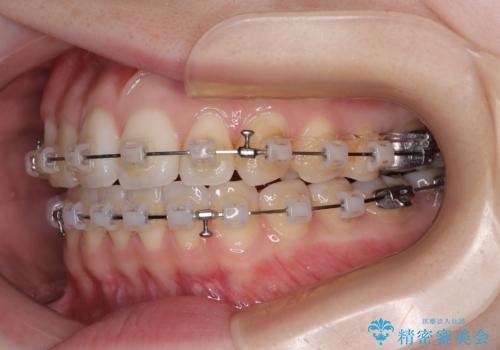

- クリアブラケット

- 前歯のデコボコと、上下前歯が接触せずに前に飛び出していることを気にして来院された患者様です。

舌の突出癖が強く、それが原因で上顎歯列全体が前方に突出し、上下前歯が接触できない状態となっていました。

補助装置を用いて上顎臼歯を後方移動させ、歯列を整えながら前歯部の接触を図ることとしました。

舌の突出癖改善のためのトレーニングを指導しながら、ワイヤー装置にて矯正治療を行うこととしました。